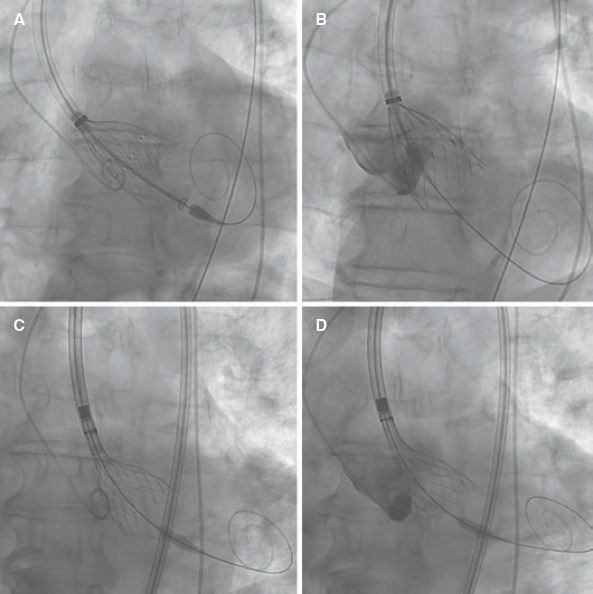

["Tailored TAVI": the importance of the deployment mechanism].